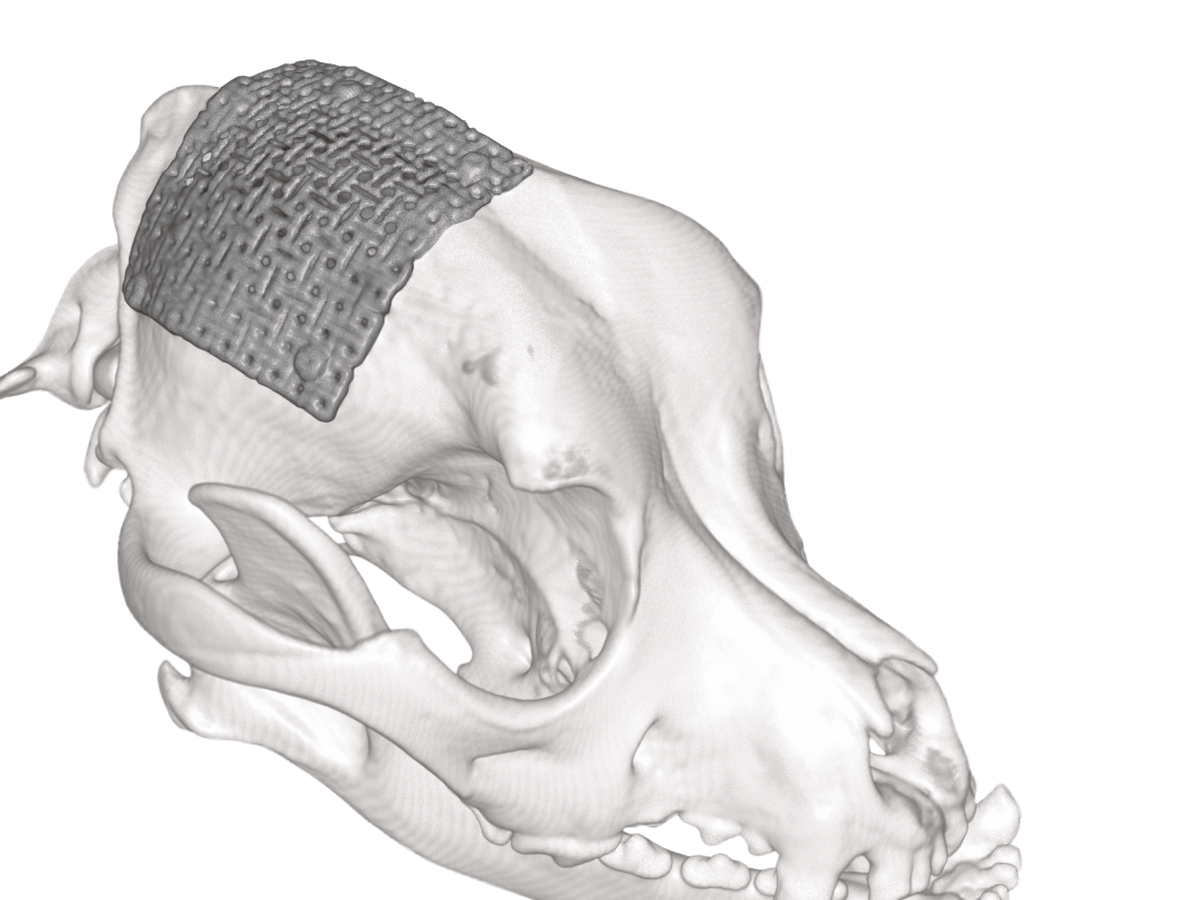

neuromesh™ is a cuttable, medical grade titanium cranioplasty solution which can be moulded to match the skull shape of each individual patient, regardless of their size.

neuromesh™ provides for the ability of "on site" engineering, allowing the surgeon more versatility when faced with repairing skull defects or maxillofacial reconstruction. It can be used to maintain the aesthetic appearance of the patient, provide for structural support and protect the brain when surgery requires the removal of excessive amounts of skull. It saves time and opens the door to more advanced cranioplasty procedures.

• Comes in single sheets of 100mm x 100mm

• Sheet is thickness of 0.6mm

Cuttable and easy to contour makes neuromesh™ a perfect solution for the reconstruction of cranial defects. Easily adaptable to contour to the anatomical curvature of craniums all varying shapes and sizes and uses low-profile titanium screws for fixation.